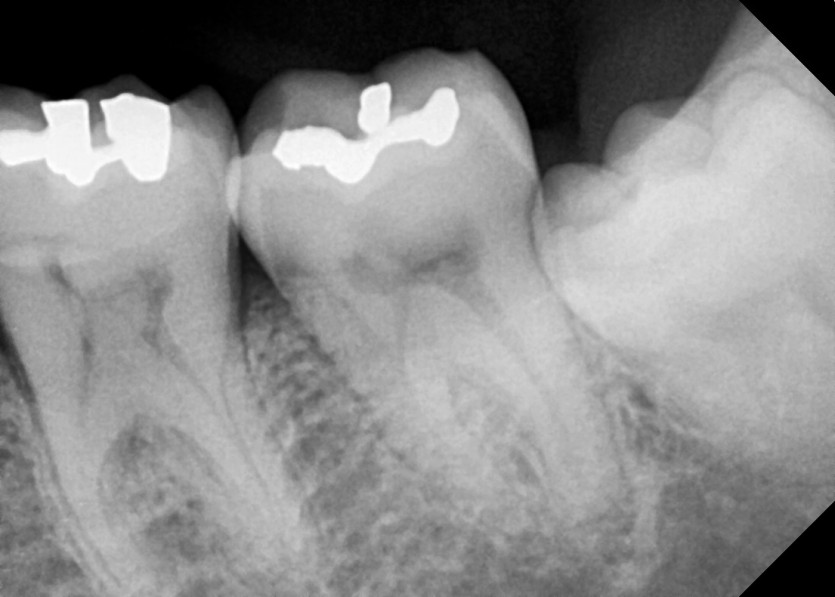

#28,38,48 사랑니 발치

구강 외과 전문의가 당일 발치했습니다.